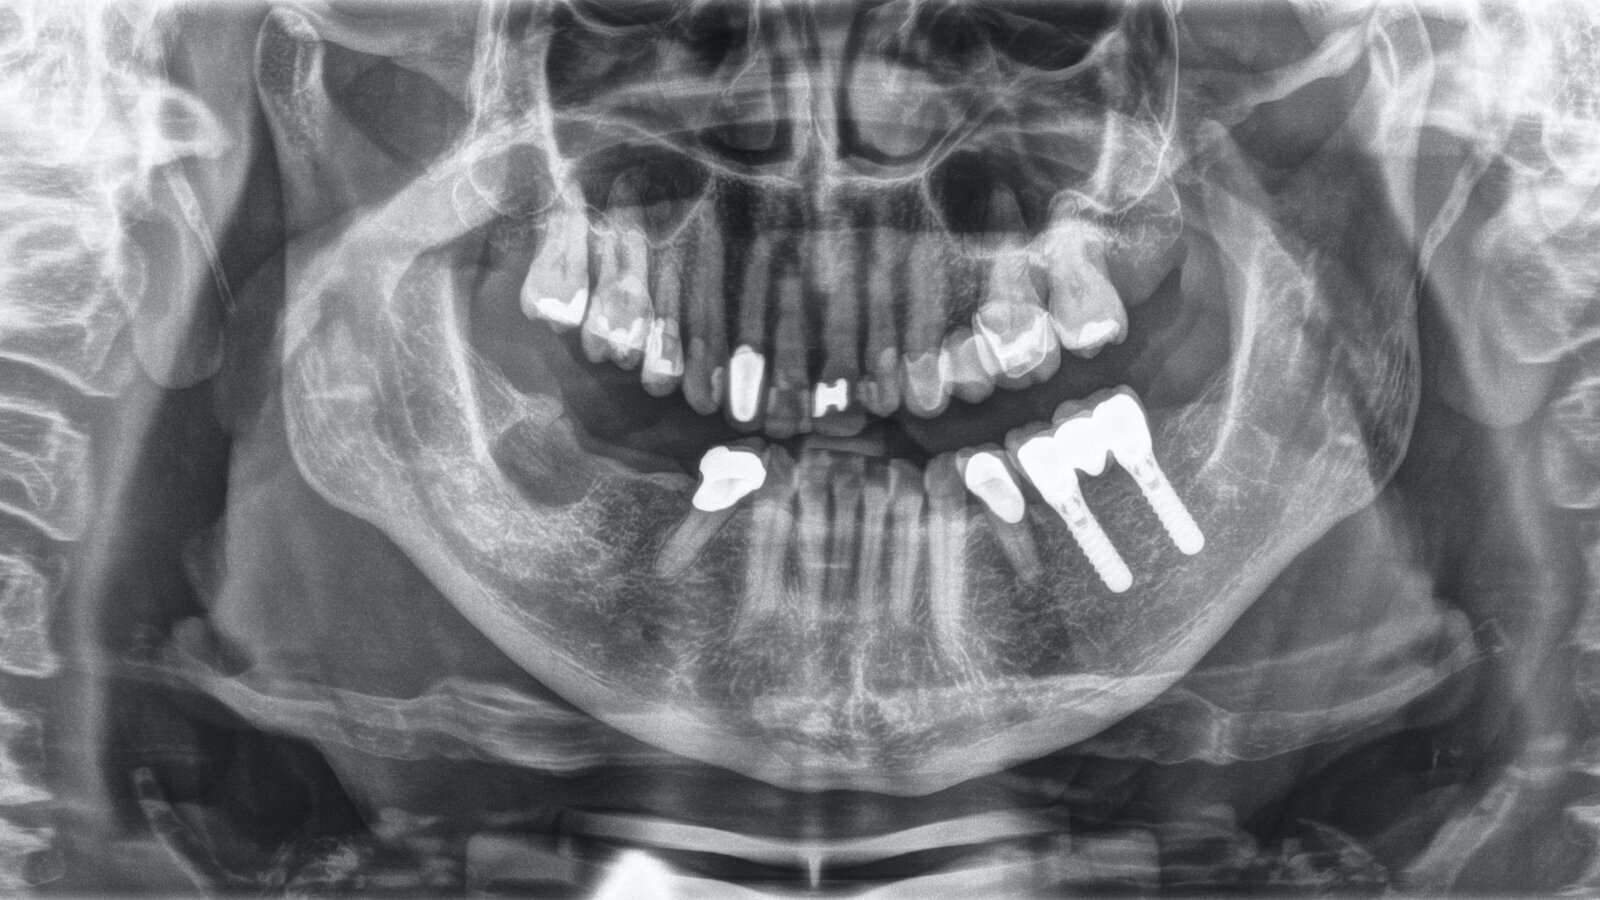

Radiografía de una paciente con buena salud oral y enfermedad periodontal temprana al que se lo trató siguiendo el Concepto de Prevención Personalizada.

Paciente de 68 años sin enfermedades previas relevantes de salud general que no toma medicación; sus hábitos alimenticios tampoco suponen un riesgo especial. La paciente tiene dos implantes (tercer cuadrante, desde hace cinco años) y enfermedad periodontal previa (periodontitis en etapa IV, grado B) con pérdida dental. Actualmente las condiciones periodontales son estables, pero la periodontitis aumenta de manera determinante las complicaciones biológicas cuando se realizan implantes y puede ocasionar la pérdida de un implante. Para la sesión de profilaxis se hacen cuatro recomendaciones.